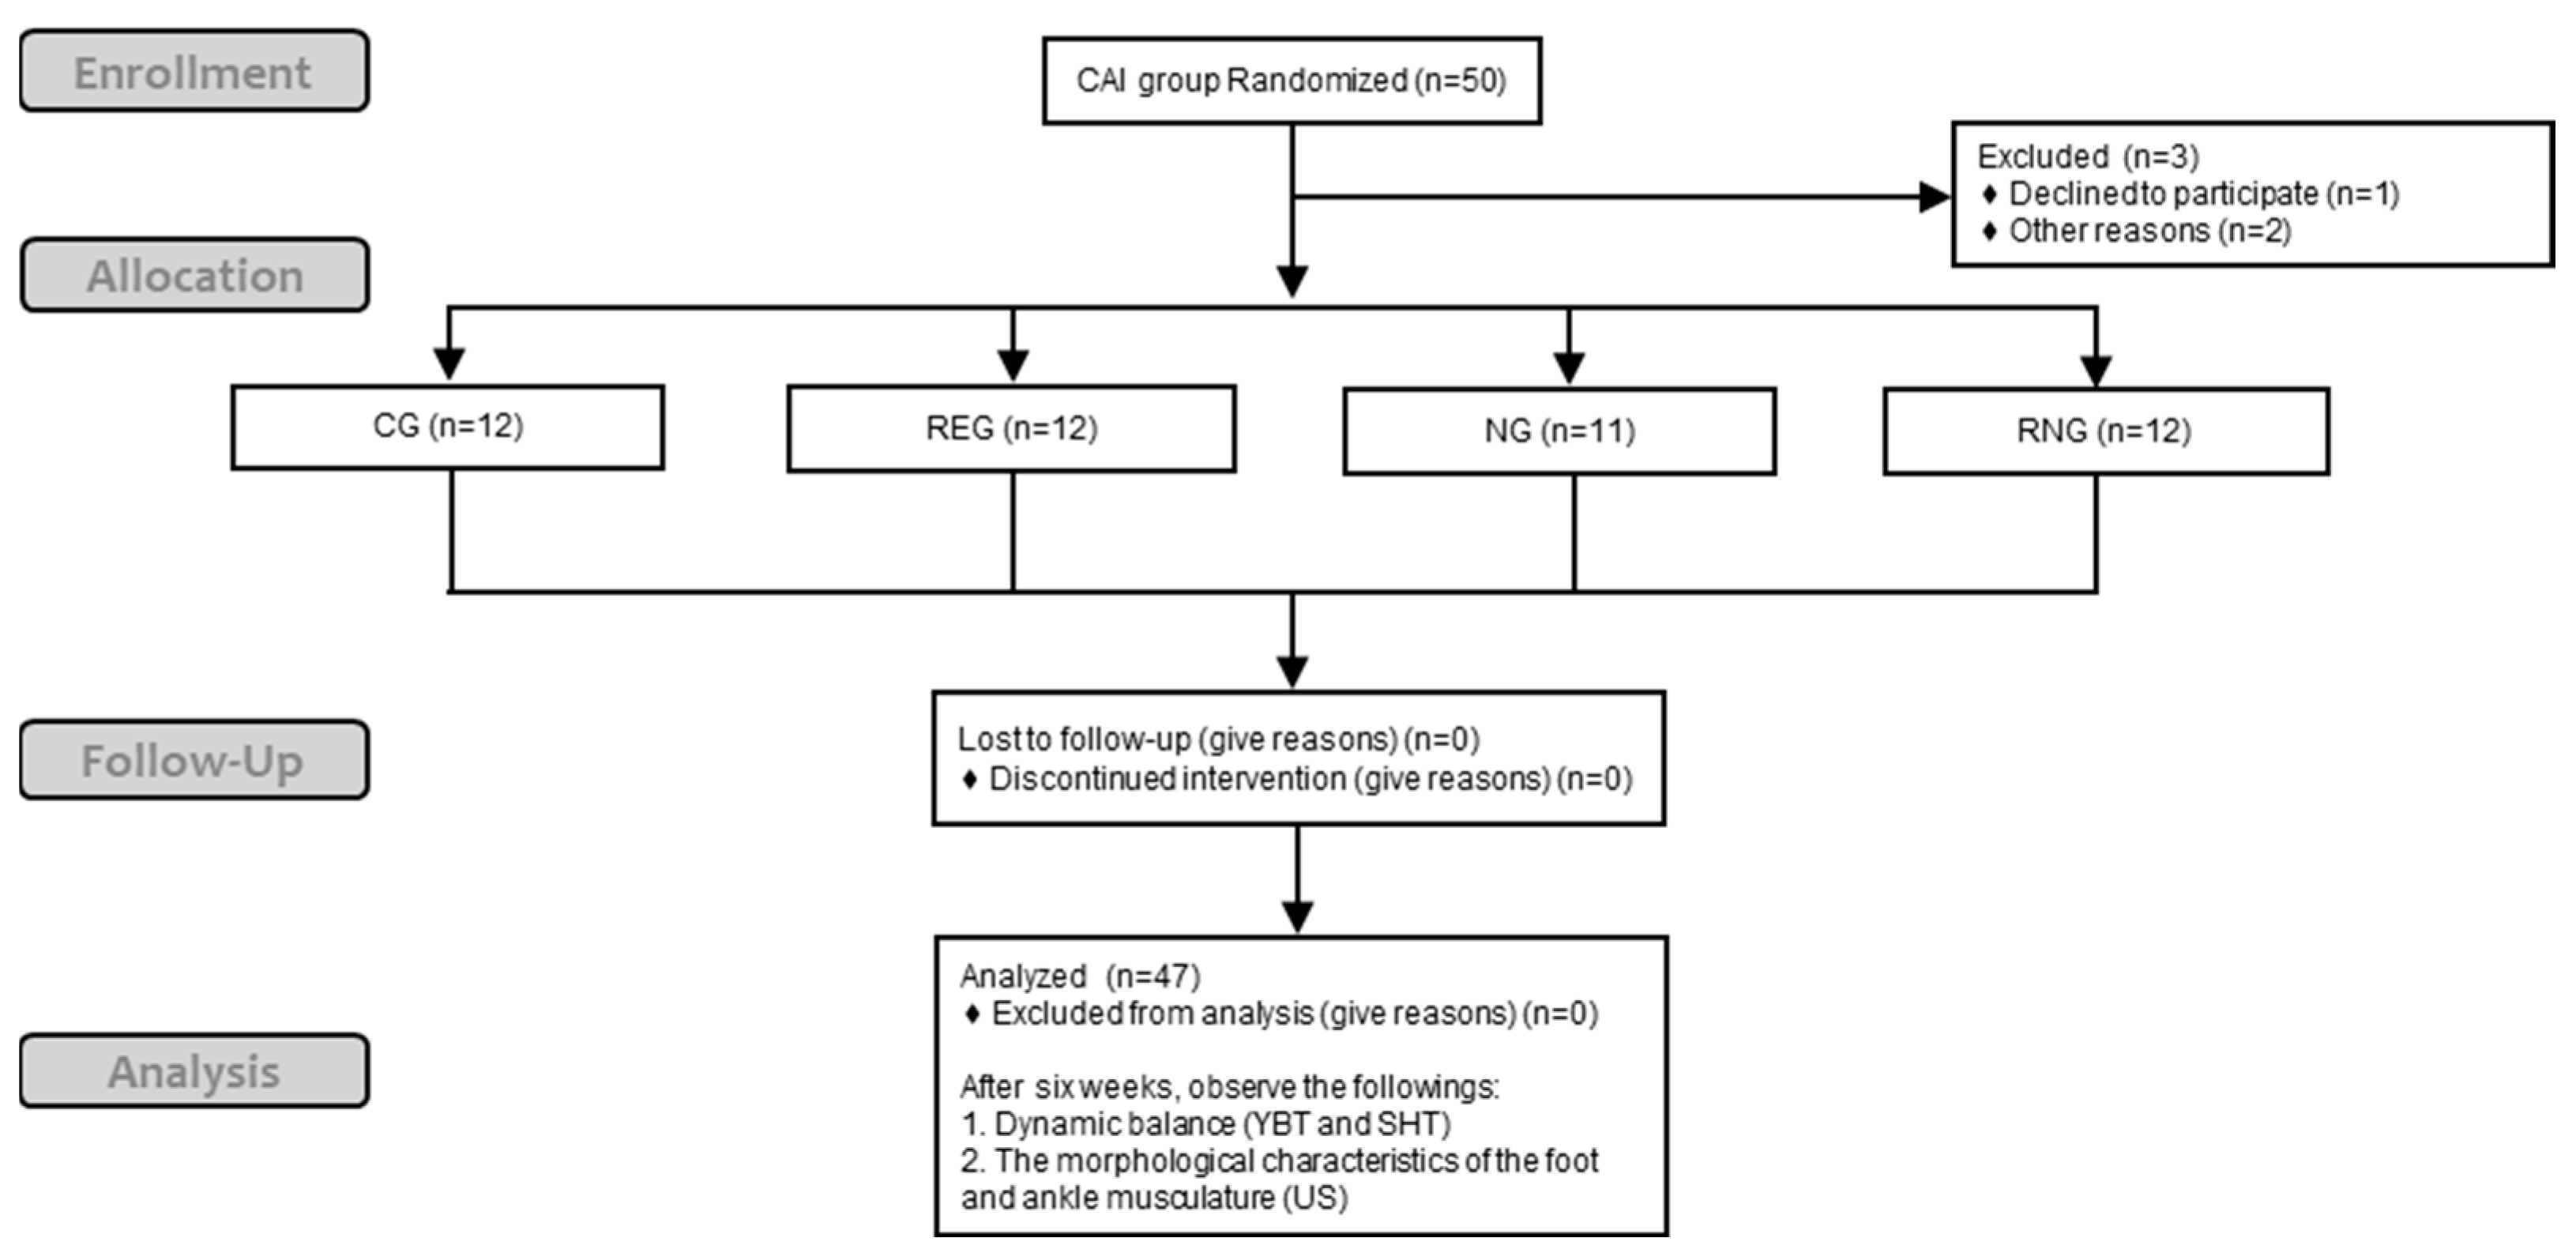

2. Materials and Methods

2.1. Study Design

2.2. Participants

2.3. Procedure